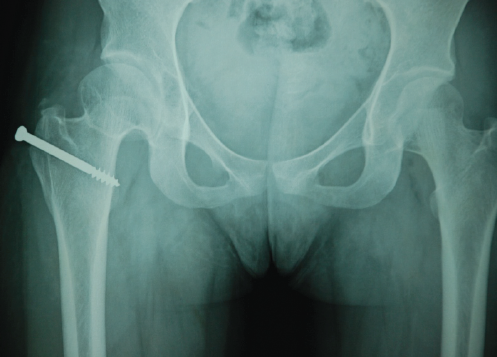

Based on clinical presentation and imaging findings consistent with synovial chondromatosis, surgical intervention was undertaken using the Ganz safe surgical dislocation technique. This approach was selected to provide optimal visualization of the entire joint space while minimizing the risk of avascular necrosis of the femoral head. The procedure was performed through a posterior approach with trochanteric osteotomy, allowing controlled dislocation of the femoral head while preserving the medial femoral circumflex artery and its contributions to femoral head vascularity (Fig. 2a and b).

Figure 2: (a) Dislocated femoral head drilled with K-wire. (b) Vascularity of the femoral head confirmed through bleeding.

Ganz osteotomy preserves the external rotators (specifically obturator externus), which act as a protective sling around the medial circumflex femoral artery branch. Dislocation of the femoral head was done in a controlled, anterior direction (after posterior approach entry), so the posterior retinacular vessels remain untensioned and intact. The capsule was opened in Z-shaped fashion, avoiding transection of the retinacular vessels. Intraoperatively, 14 osteocartilaginous loose bodies ranging from 5.0 to 25 mm in diameter were identified and completely removed from the joint space (Fig. 3).